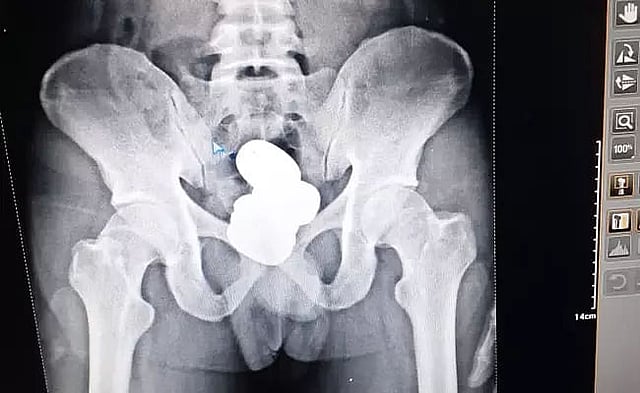

After a preliminary investigation, the CISF officials took him to a medical examination for an X-Ray of his lower body and which showed concealed metallic items inside his body cavity.

The CISF officials said that four packets of yellow metal paste weighing about 909.68 grams were recovered inside the rectal cavity of a passenger.